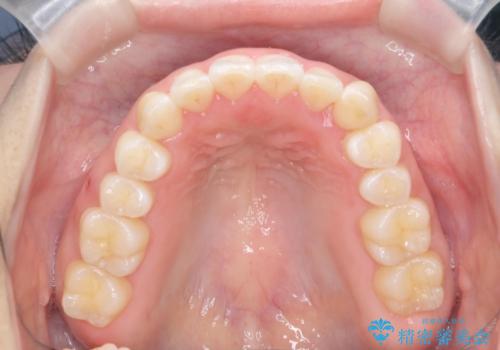

八重歯を非抜歯で マウスピースで治療 奥歯を後ろに下げてすき間を確保

- 八重歯を主訴に来院。

奥歯を後ろに下げてすき間を確保し、八重歯を引っ込めて並べる治療を行いました。

奥歯を後ろに下げるために、矯正用のミニスクリューを使用しています。

かなり真面目に使っていただいた印象で、綺麗に動きました。